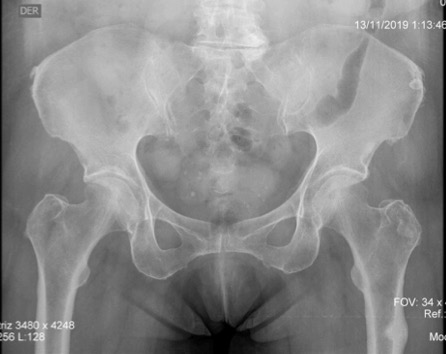

Radiografía de pelvis en proyección AP, donde se evidencia un engrosamiento de la cortical lateral a nivel subtrocantérico en el fémur izquierdo, sin cambios en el fémur contralateral.

Figura 2: Radiografía de pelvis en proyección AP, donde se evidencia un engrosamiento de la cortical lateral a nivel subtrocantérico en el fémur izquierdo, sin cambios en el fémur contralateral.

Fuente: los autores.